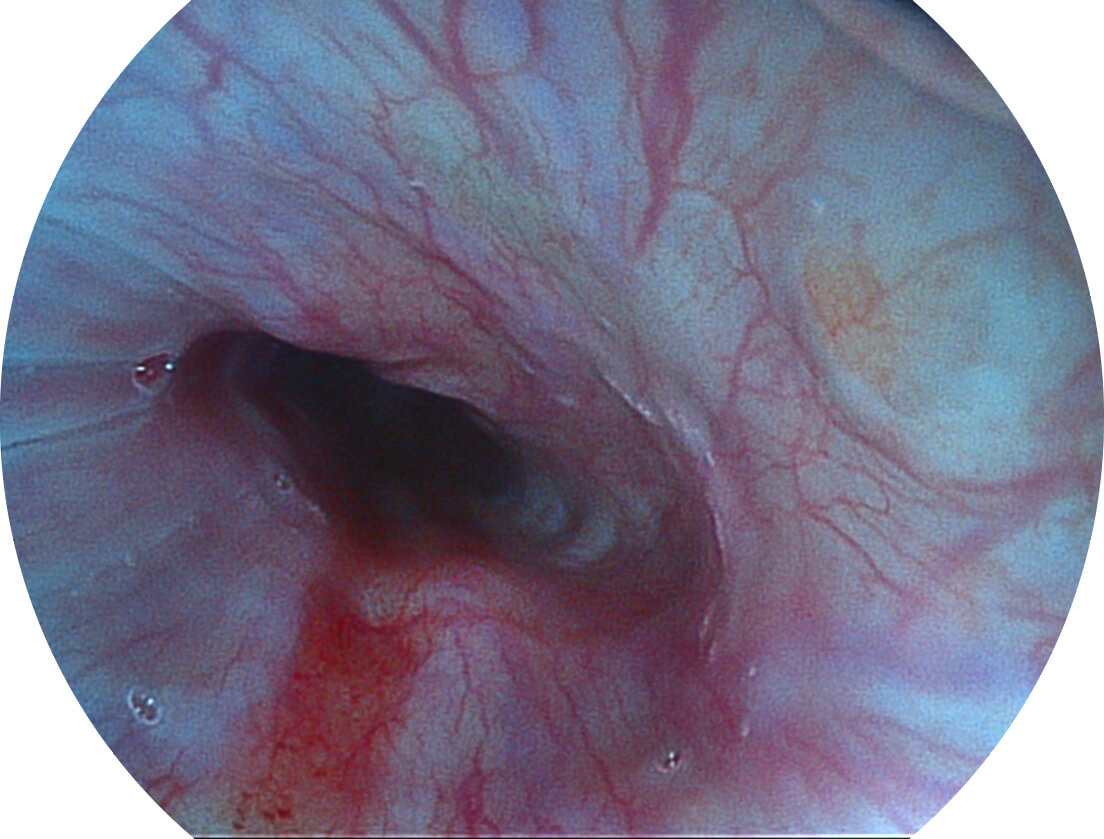

白光图像

VIST图像